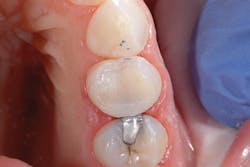

Figure 4: Final restoration on tooth No. 12

After light curing the Prime&Bond Elect for 10 seconds, the composite resin material was placed, occlusion checked, and the restoration completed (figure 4). Six months later, the patient returned for a hygiene recall appointment and reported no negative postoperative sequelae with the restoration on tooth No. 12. Bitewing radiographs were taken as a part of the exam. Not only did the restoration show excellent adaptation to the internal cavity walls, but no voids or black lines indicative of a thick adhesive layer were present (figure 5).